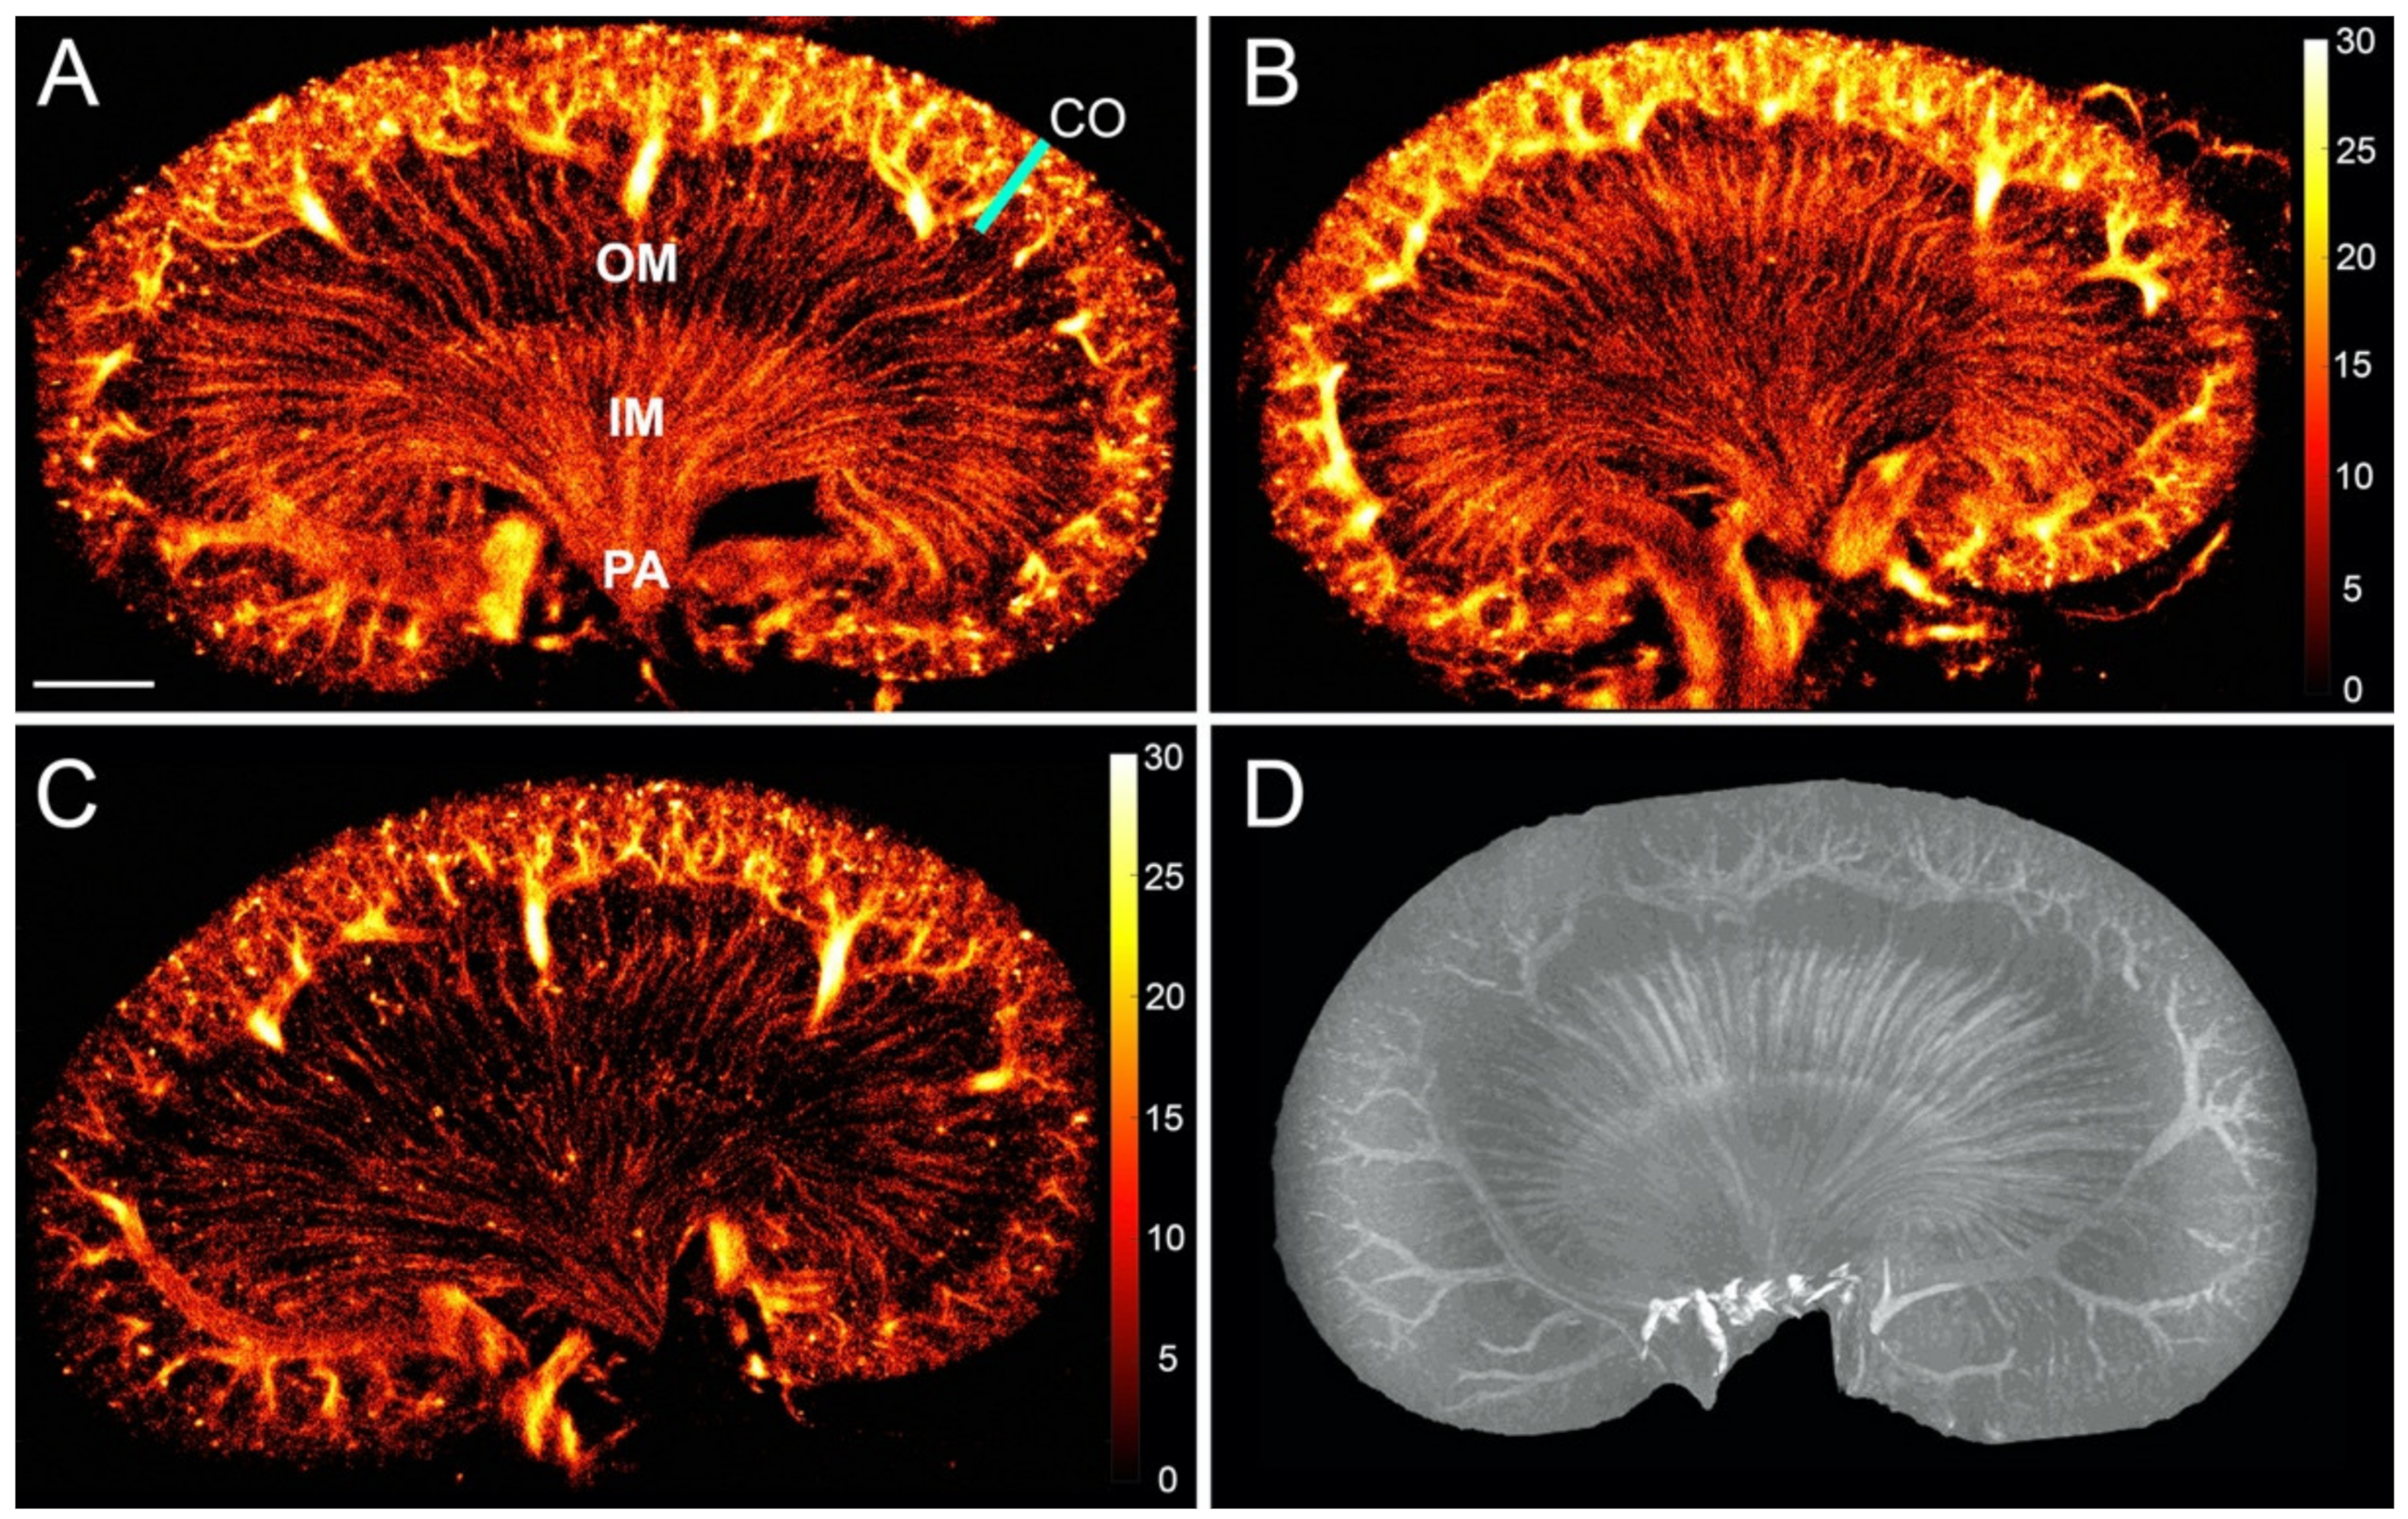

3.1. The Healthy Renal Microvasculature